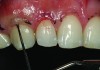

A 55-year-old woman presented with root decay along the left lateral incisor (tooth No. 10) and canine (tooth No. 11) (Figure 1). It was proposed that invisible Class V restorations be placed using an MMID procedure. There are several keys to attaining a successful invisible Class V restoration. Proper understanding of composite resin shade selection, preparation design, and sequence of composite resin layering are important to achieve an ideal blending of the composite resin to the existing tooth. Correct finishing and polishing technique is equally essential in obtaining a seamless esthetic restoration.3,11

Shade selection is always completed before initiating treatment; this is important to develop the proper shade-layering sequence. Composite shades were placed directly on the tooth and shades that matched the areas of the tooth being restored were chosen (Figure 2). To achieve an invisible Class V restoration, a more complex layering process is needed to blend the composite resin.

Total removal of the decay was performed. To keep the preparation minimally invasive, a caries indicator (Seek®, Ultradent Products, Inc., www.ultradent.com) was used so that only the infected dentin was removed. Minimally invasive burs (Micro Prep Kit, Komet USA, www.kometusa.com) were used, which are helpful when minimal tooth removal is an objective (Figure 3). A long-bevel margin (889M-007, Komet USA) was then created along the facial side so that the final composite resin could be blended to the existing dentition. A thin layer of resin-modified glass ionomer (RMGI) (GC Fuji II™ LC, GC America Inc.) was sculpted and light-cured to cover the affected dentin.

CASE 1 INITIAL RESTORATION STEPS (1.) Extensive root decay along teeth No. 10 and No. 11. (2.) Composite resin try-in was done to develop final layering sequence. (3.) Teeth were isolated and minimally invasive preparations were completed with minimally invasive burs. (4.) After a thin liner of resin-modified glass ionomer was placed, dentinal adhesive was bonded to the root in preparation for composite placement. (5.) To match the chromaticity along the gingival aspect, an opacious dentin shade (AO2) was bonded over the resin-modified glass ionomer to mimic the lost dentin.